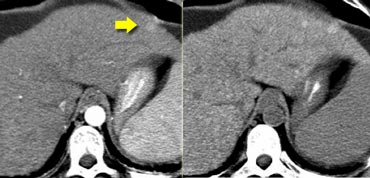

Metastasis difficult to detect on CECT in portal venous phase (left). Better seen on NECT. Metastasis difficult to detect on CECT in portal venous phase (left). Better seen on NECT.

Metastases in fatty liver

Focal fatty sparing in a diffusely fatty liver or foci of focal fatty infiltration can simulate metastases.

However on nonenhanced scans these regions of fat variation tend to be nonspherical and geographic, with no mass effect or distortion of the local vessels.

On the other hand a fatty liver can also obscure metastases.

On a contrast enhanced CT hypovascular lesions can be obscured if the liver itself is lower in density due to fat deposition. On a NECT these lesions usually are better depicted (figure).

Steatosis of right liver lobe. No lesions detectable. On US multiple lesions in the same region. Steatosis of right liver lobe. No lesions detectable. On US multiple lesions in the same region.

If a patient is known to have a fatty liver, it is better to do an MRI or ultrasound for the detection of livermetastases.

On the left a patient with fatty infiltration of large parts of the liver. No metastases were seen, but on an ultrasound of the same region multiple metastases were detected.